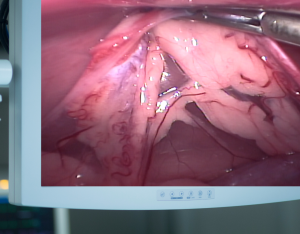

O objetivo do curso é trazer uma nova realidade para o paciente canino e felino. Mais do que pequenas incisões o que queremos é promover a aliança entre tecnologia e capacitação. O cirurgião que invade por vídeo traz aumento de 25x na visão, qualidade full hd ou 4K, melhor que o olho humano, manobras precisas com uso de instrumental que ajustam as nossas mãos e uso de eletricidade para hemostasia e dissecção. Tudo isso com mínima invasão, máxima visualização, garantias assépticas e controle de dor.